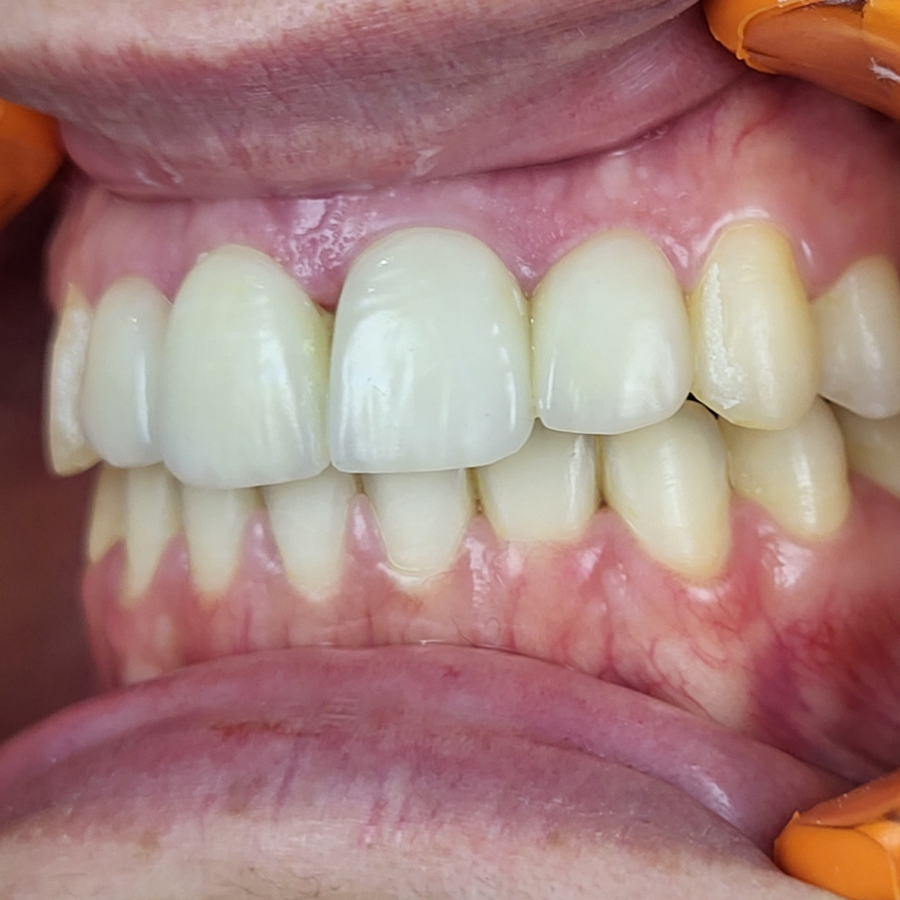

Réhabilitation esthétique après orthodontie : full-zircone & disilicate de lithium

Une jeune patiente arrive en fin de traitement orthodontique pour un déficit esthétique.

La difficulté réside dans la réalisation de prothèses différentes dans le même secteur : jongler avec la full-zircone et le disilicate de lithium.

Ce challenge fut le sujet de mon mémoire du DU d’esthétique de Strasbourg en 2008.

L’expérience et l’investissement dans le digital depuis 2017 rendent le résultat plus prévisible.